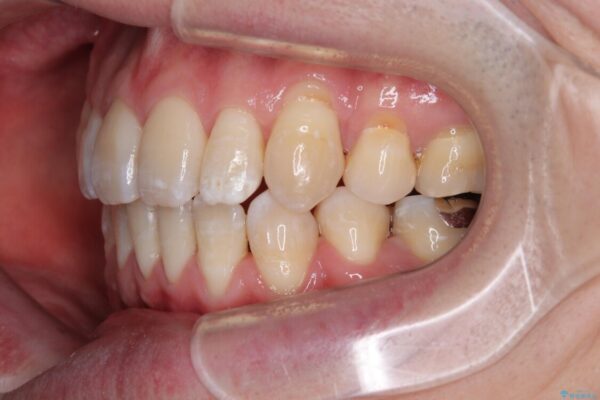

治療前

• 口元の突出感を改善!目立ちにくいワイヤー矯正で自信を持てる自然な横顔に 治療前画像